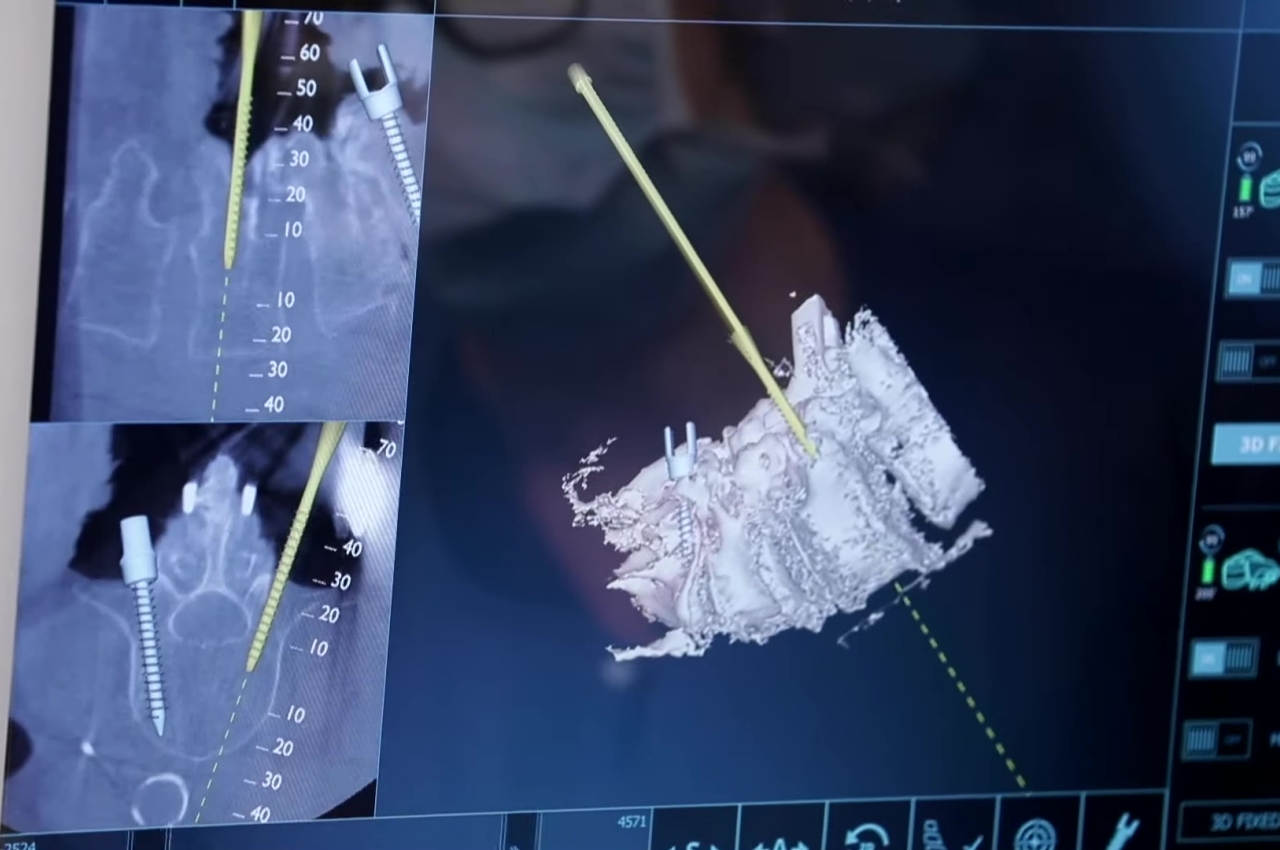

Chirurgia AR

Grazie a Hollywood, molte persone probabilmente immaginano che la chirurgia nel mondo dell'AR e del Metaverso coinvolga medici che eseguono procedure a miglia o addirittura paesi di distanza dal paziente. Anche se ciò potrebbe avere vantaggi salvavita, non abbiamo ancora bisogno di andare così lontano per raccogliere i vantaggi della tecnologia in sala operatoria. Essere semplicemente in grado di vedere più informazioni di quelle che abbiamo fisicamente di fronte fa molto per migliorare la nostra conoscenza e comprensione, che è davvero il cuore della realtà aumentata, senza clamore e sensazionalismo.

I medici richiedono molta immaginazione quando lavorano sui pazienti e non nel modo in cui voli di fantasia. Potrebbero non avere una visione chiara di ciò su cui stanno operando o devono lavorare con materiali microscopici che sarebbero impossibili da vedere ad occhio nudo. Sebbene questi professionisti lavorino in questo modo da decenni, ciò non significa che le cose debbano rimanere così, soprattutto se la tecnologia può aiutare ad alleggerire il carico.

Gli interventi chirurgici assistiti da AR sono già stati eseguiti con molto successo, ma spesso non si sente parlare di quelli in contrasto con le notizie su questa o quella nuova piattaforma Metaverse. Essere in grado di vedere dove perforare un osso o dove mettere una vite può rendere le procedure più rapide e sicure. Ovviamente, avrai bisogno di occhiali AR migliori per farlo accadere perché gli attuali modelli di consumo che abbiamo semplicemente non lo taglieranno sul tavolo operatorio, gioco di parole.

Progettista: Augmedics (via Medicina John Hopkins )